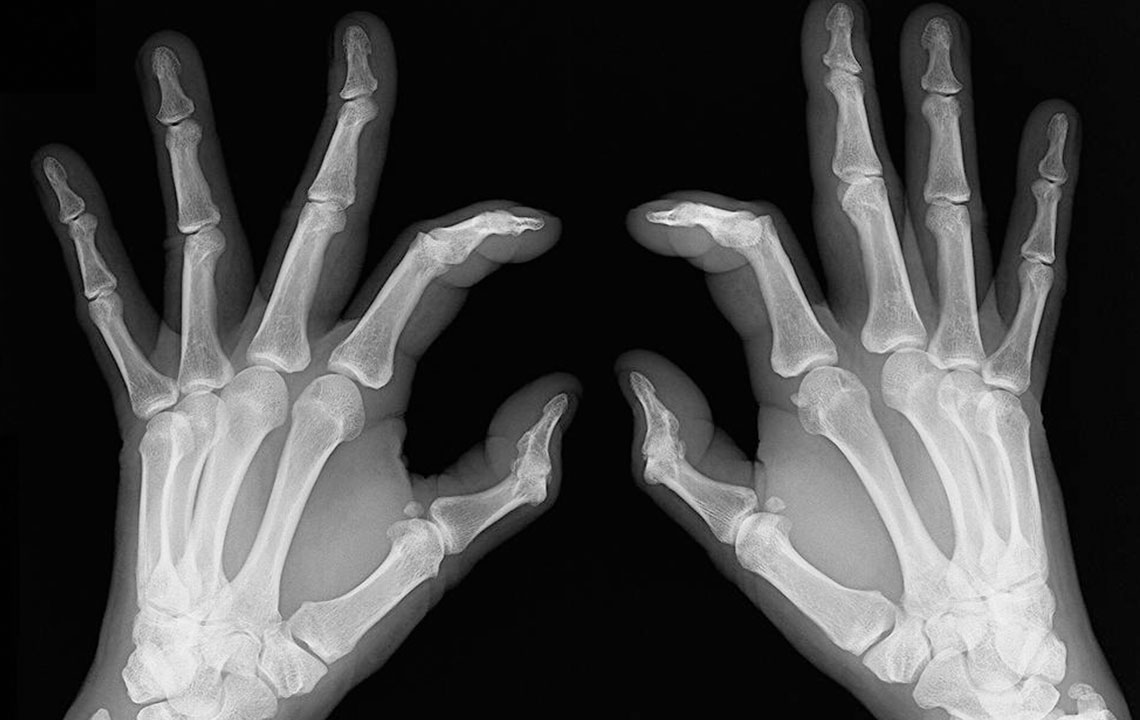

Early signs of rheumatoid arthritis and how to catch them

Rheumatoid arthritis causes chronic inflammation of joints, which results in joint pains, inflammation and bone deformation. It usually starts slowly with pain in some parts of the body that can come and go in the beginning and then spread within weeks or months. It is better in this day and age to always be aware of your health problems and not to ignore slightest of joint pains. The symptoms can vary from one person to another. Here are the many rheumatoid arthritis symptoms that you can check out.

People who have rheumatoid arthritis often wake-up early in the morning complaining of stiff joints and restricted movement. The mobility is back slowly and with little joint movements . Joint redness: Sometimes the troubled area also experiences redness and feels warm to the touch. However, make sure the redness is not due to reasons such as a bruise or a scrape of the skin. Bone deformation: Arthritis also attacks the bones and makes them crooked and stiff. Look out for signs of any subtle changes in your joints and test them for pain levels.